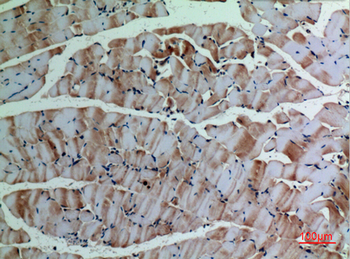

α-SMA Polyclonal Antibody

Catalog Number: orb1411650

| Catalog Number | orb1411650 |

|---|---|

| Category | Antibodies |

| Description | Rabbit polyclonal antibody to α-SMA. |

| Clonality | Polyclonal |

| Species/Host | Rabbit |

| Conjugation | Unconjugated |

| Reactivity | Human, Mouse, Rat |

| UniProt ID | P68133 |

| Tested applications | IHC-P, WB |

| Dilution range | WB: Western Blot: 1/500 - 1/2000. IHC-p: 1:100-300 ELISA: 1/20000. Not yet tested in other applications. |

| Storage | Maintain refrigerated at 2-8°C for up to 2 weeks. For long term storage store at -20°C in small aliquots to prevent freeze-thaw cycles |

| Alternative names | ACTA1; ACTA; Actin, alpha skeletal muscle; Alpha-a Read more... |

| Note | For research use only |